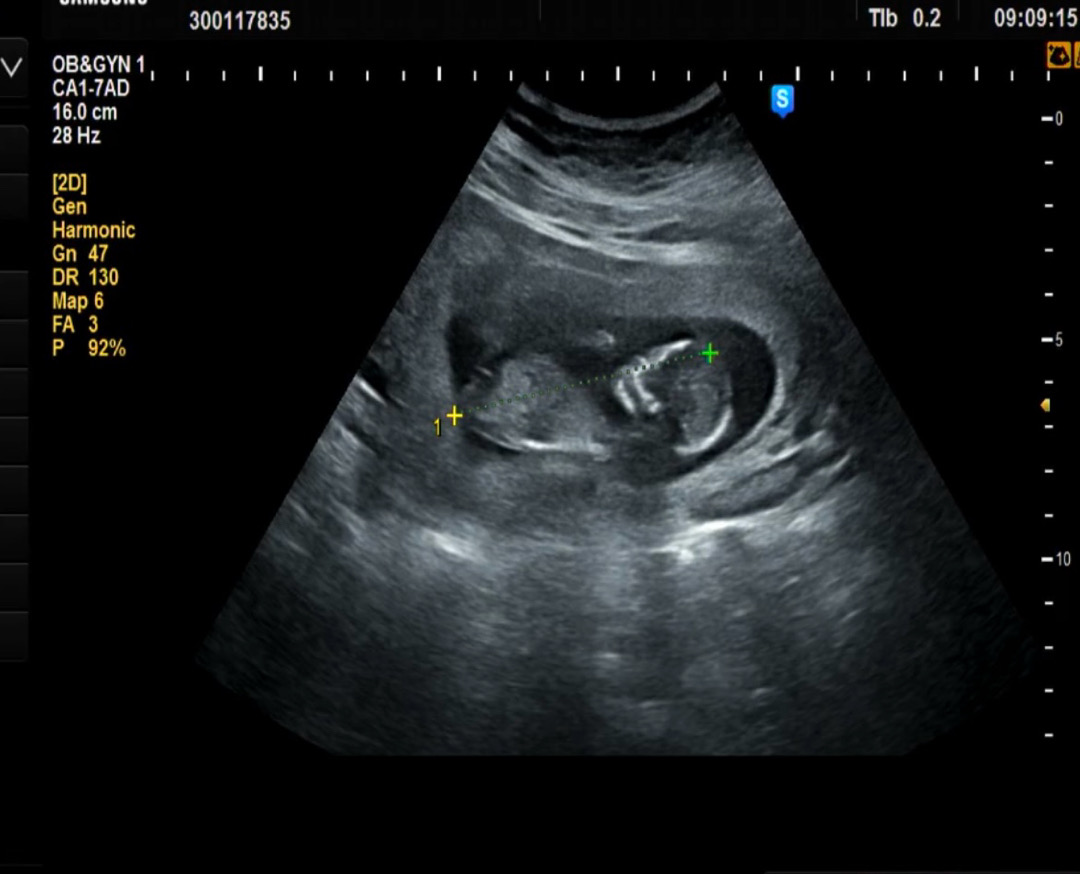

12주차 각도법!? 봐주세욘!

성별이 보이시나요?? 저만 잘 안보일까요ㅠ